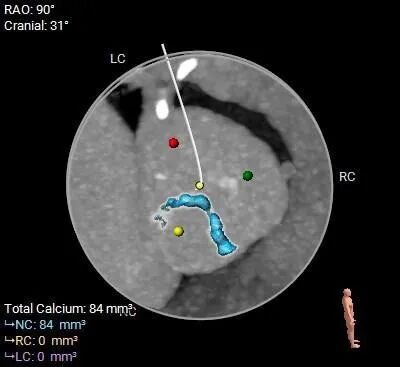

钙化评估

• 三叶式主动脉瓣,瓣叶增厚,R-L交界增厚粘连,轻度钙化,钙化主要沿无冠窦瓣缘分布;LVOT近似直筒型;

• 左、右冠高度可,切线位测量,左窦瓣叶稍长于左冠开口下缘;左主干及前降支可见部分钙化斑块;